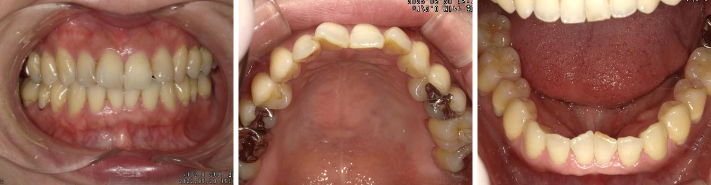

について報告をさせていただきます!施術前の写真がこちら